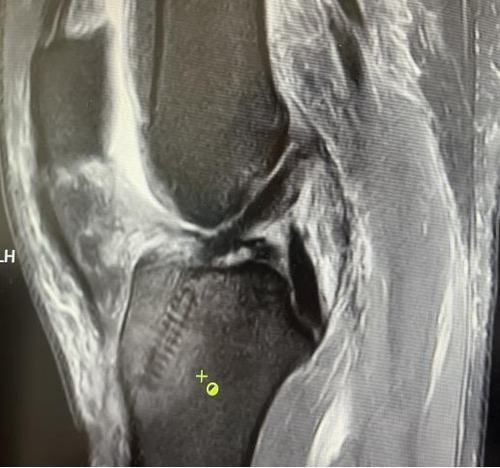

术后X线片

术后磁共振

镜下重建前交叉韧带走形、张力良好

经患者同意后,李鹏主任手术团队制定详细手术方案。手术如期进行,经团队密切配合,对几位患者分别顺利完成关节镜下膝关节镜镜检、关节清理、股薄肌半腱肌取腱移植术、前交叉韧带重建术、软骨损伤微骨折术、半月板缝合修整术等。